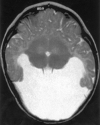

Background and purpose: Analysis of specific features in the brain of patients with holoprosencephaly (HPE) may clarify normal and abnormal brain development and help predict outcomes for specific children. We assessed sulcal and gyral patterns of cerebral cortex in patients with HPE and developed a method of grading brain development.

Methods: Neuroimaging studies (75 MR imaging, 21 CT) of 96 patients with HPE were retrospectively reviewed, with specific attention paid to the cerebral cortex. Thickness of cortex, width of gyri, and depth of sulci were assessed subjectively and by measurement. The angle between lines drawn tangential to the sylvian fissures ("sylvian angle") was measured in each patient with HPE and in 20 control patients.

Results: Thickness of cortex was normal in all 96 patients. Gyral shape and width and sulcal depth were normal in 80 patients. Twelve patients, all with very severe HPE and microcephaly, had reduced sulcal depth, diffusely in eight and limited to the anteromedial cortex in four with lobar HPE. Four patients had subcortical heterotopia, located anterior to the interhemispheric fissure, associated with shallow sulci in the overlying cortex. Sylvian fissures were displaced further anteriorly and medially as HPE became more severe, until, in the most severe cases, no sylvian fissures could be identified. Sylvian angle measurements corresponded closely with severity of HPE, being largest in the most severe and smallest in the least severe cases. All patients with HPE had sylvian angles significantly larger than the mean of 15 degrees measured in the control patients.

Conclusion: The only true malformations of cortical development were subcortical heterotopia. However, diffuse and focal abnormal sulci were observed. We propose our sylvian angle measurement of extent of frontal lobe development as an objective means of quantifying the severity of HPE.